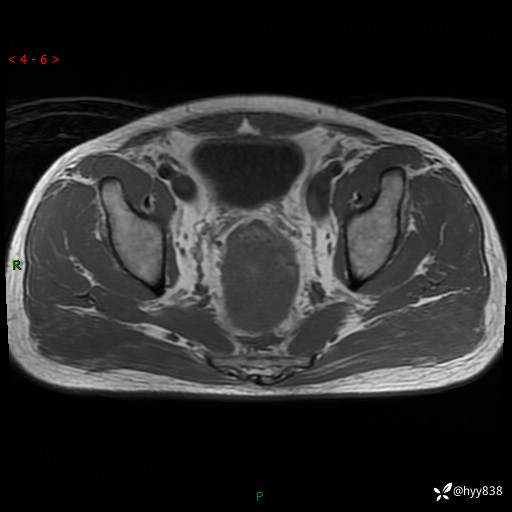

盆腔MRI平扫